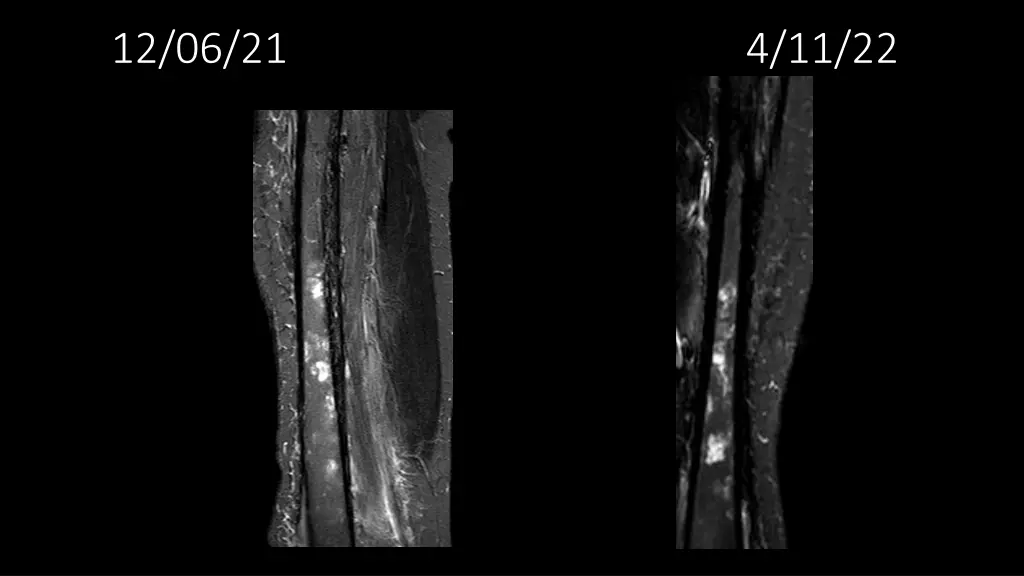

62-year-old shows post-surgery progress from 11/4/2020 to 4/11/22

Explore the journey of a 62-year-old individual post-UPS resection on 11/4/2020, through a series of dated images leading up to 4/11/22. Witness the transformation and recovery process in these visual updates reflecting the progression over time.